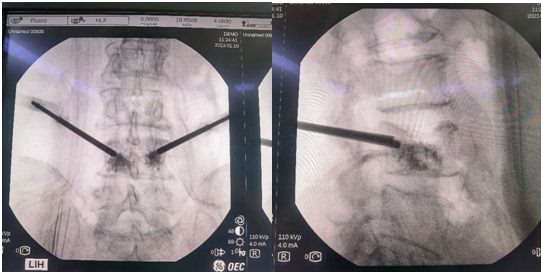

患者为70岁女性,腰部疼痛伴活动受限10天,在黑料网经MRI及CT检查示:腰4椎体压缩性骨折。经专家讨论后,医疗团队拟采用机器人辅助,局麻下行经皮球囊扩张椎体成形术。经过精密的仪器调试和配准,术前进行了反复的模型演练。刘时璋主任团队将患者的CT数据与机器人系统配准,工程师团队将事先规划好的个体化穿刺路径数据植入机器人系统。将术中的正侧位X线透视数据与CT数据融合后,机械臂按照术前规划路径,一次性穿刺成功,位置精准满意。

传统手术徒手穿刺需要在反复透视下,多次调整穿刺位置、方向及深度,增加了患者的不适感,且不一定能够达到理想的穿刺位置。而此例患者在脊柱机器人的辅助下,穿刺针精准地置入骨折塌陷位置,促使球囊扩张复位准确高效。穿刺过程中灵敏的压力反馈系统及可调的穿刺速度,大大增加了穿刺过程的安全性,使传统PKP手术更加精准、安全及高效,大大减少了术中透视次数及患者的不适感,同时为一些复杂骨折(如严重骨质疏松,骨性标识不明确;脊柱侧弯、旋转等)的个性化手术方案的实施提供了可能。前期,骨科病院也成功举办脊柱手术机器人培训会,团队认真学习并进一步认识到了骨科手术机器人良好的临床应用潜力,为此次手术的成功奠定了良好基础。